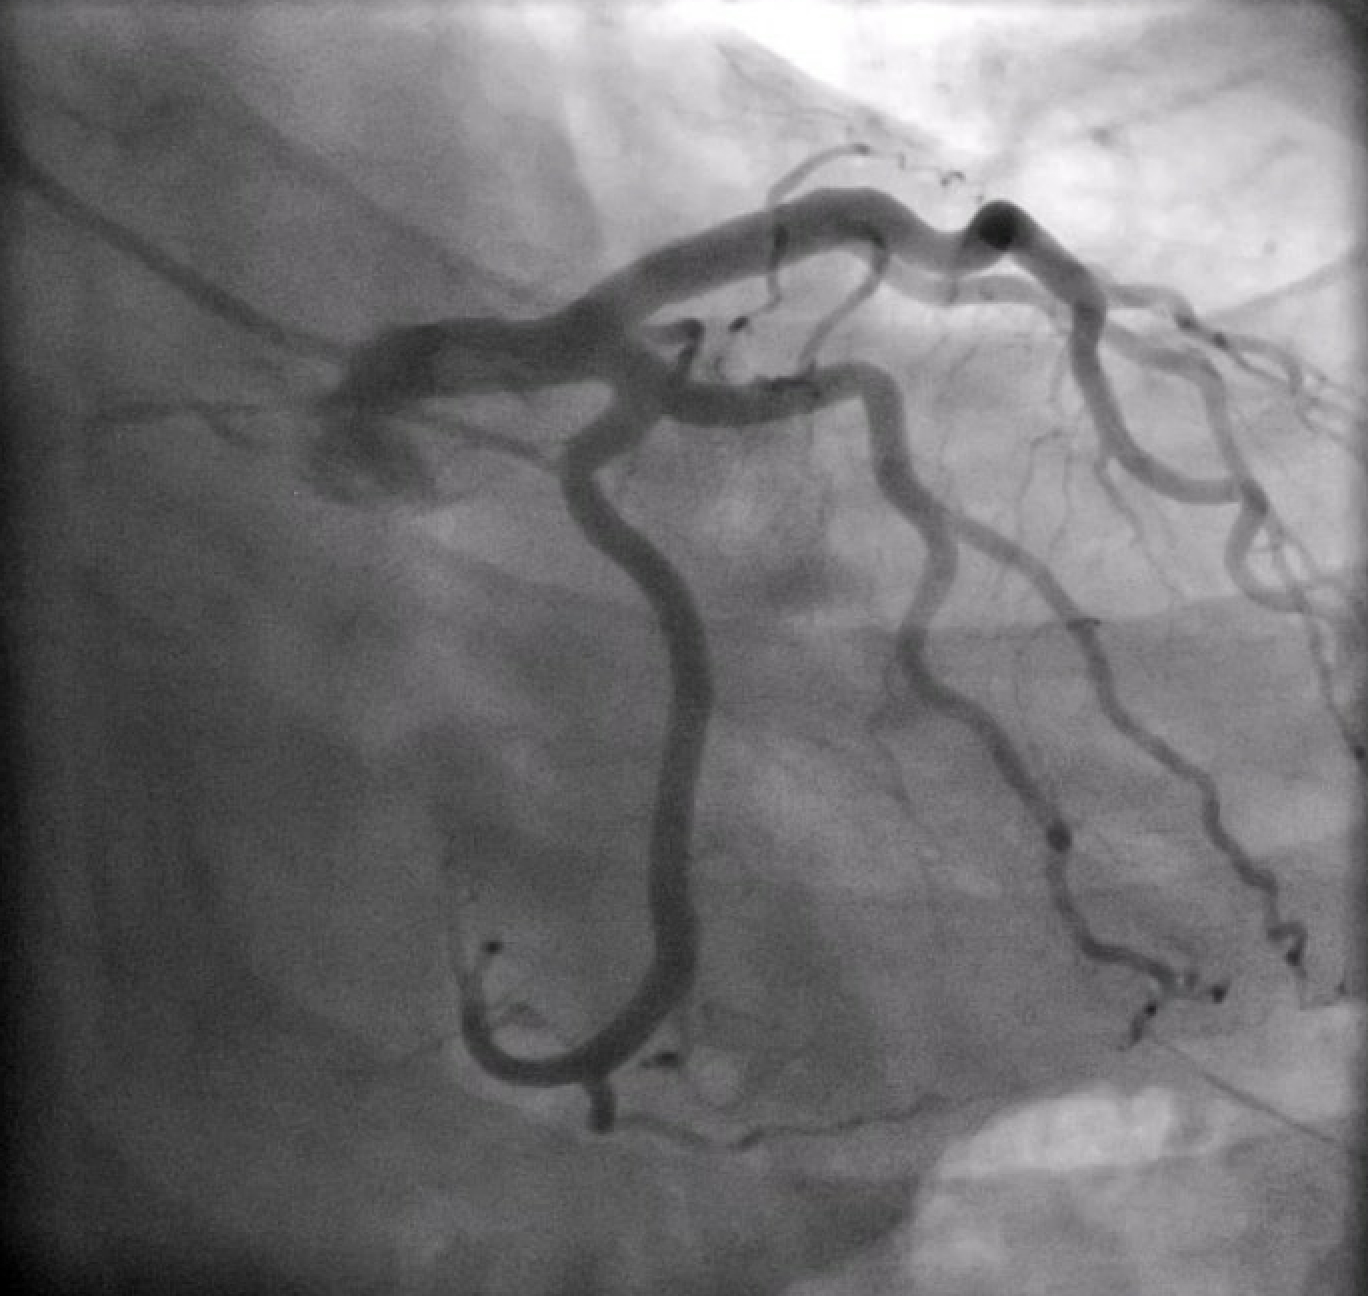

A 36-year-old male with a history of well-controlled HIV on ART, presented with fever, hypotension, and a morbilliform rash shortly after initiation of trimethoprim-sulfamethoxazole for a skin and soft tissue infection. He was found to have elevated troponins (peak 661 ng/L) and diffuse ST elevations on EKG, consistent with myopericarditis. He was vitally stable and did not complain of chest pain or shortness of breath throughout his hospital course. Initial investigation with coronary CTA revealed a possible LM thrombus, which was confirmed on left heart catheterization (LHC) as a non-obstructive thrombus (30% stenosis) in the mid-LM. The patient was managed with a tirofiban bolus and infusion, a heparin drip, and dual antiplatelet therapy with aspirin and clopidogrel. Repeat LHC five days later demonstrated complete resolution of the thrombus. TEE was performed to exclude possible sources of embolization including valvular vegetation or left ventricular thrombus. This was notable for a small mobile echodensity on the tricuspid valve which appeared to be consistent with redundant tissue, but no left-sided source of embolism, and he did not have evidence of a patent foramen ovale. The patient was discharged on apixaban and clopidogrel for 6 and 12 months respectively, with plans for outpatient cardiology follow-up and cardiac MRI.